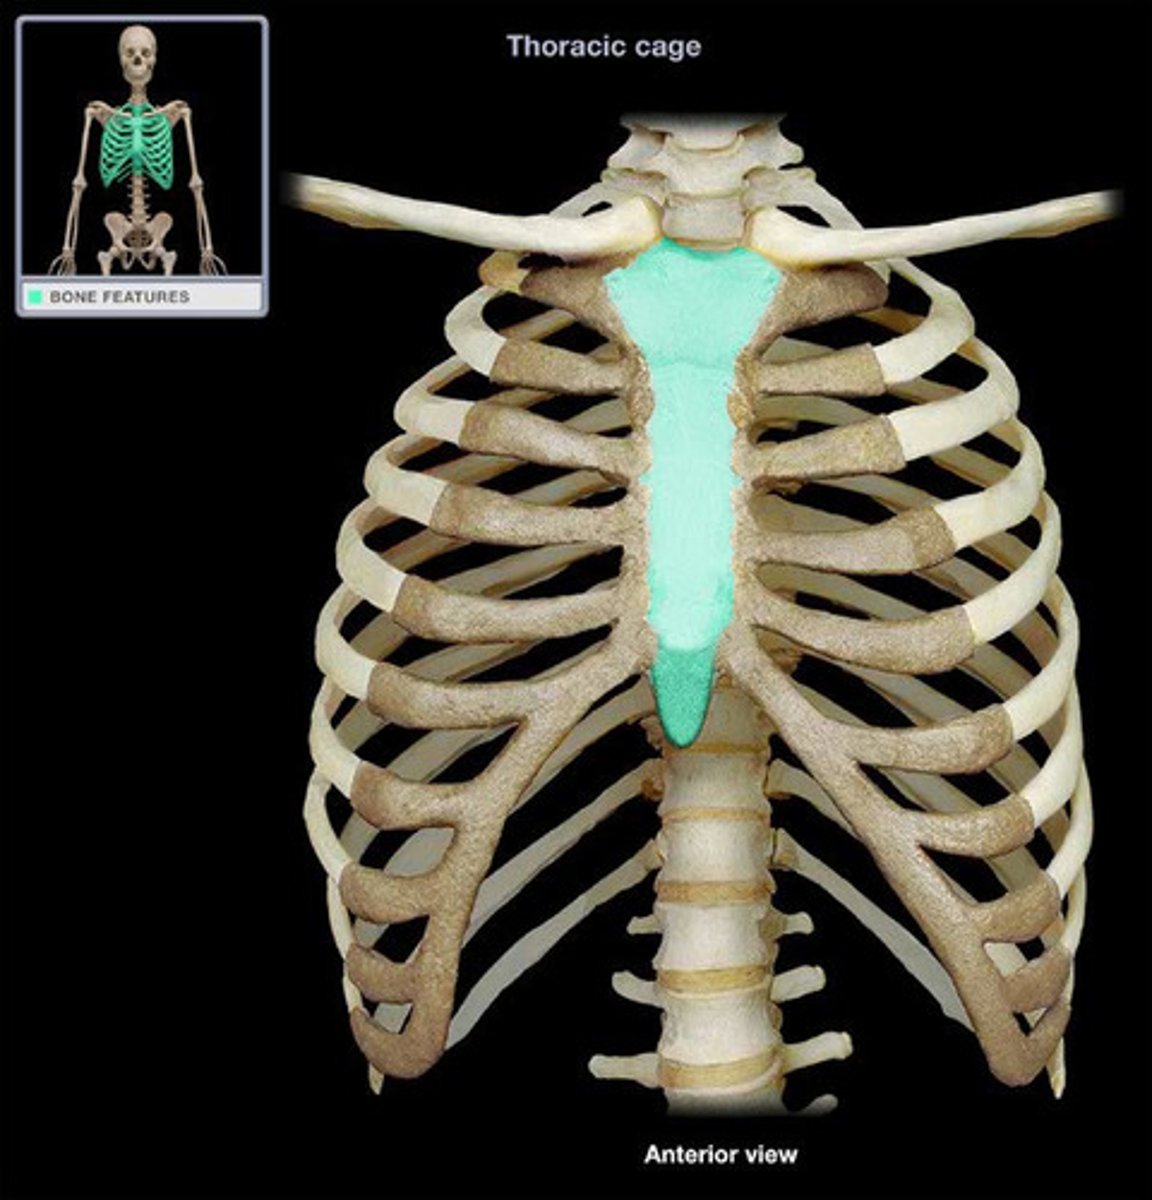

sternum

What is this bone?

body of sternum

What is this structure?

sternal angle

What is this structure?

clavicular notch

xiphoid process

What is this structure?